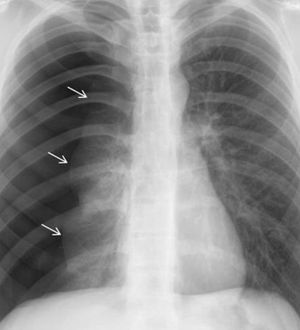

I am 99% sure it it a pneumothorax, can anyone qualified back me up?

a pneumothorax, no tension and just air and no blood in the lung

Have you seen a Pneumothorax on CXR before ? If you have , its always the same on CXR , you don't need backup , you've got this đĒ. #Spontaneous Pneumothorax.